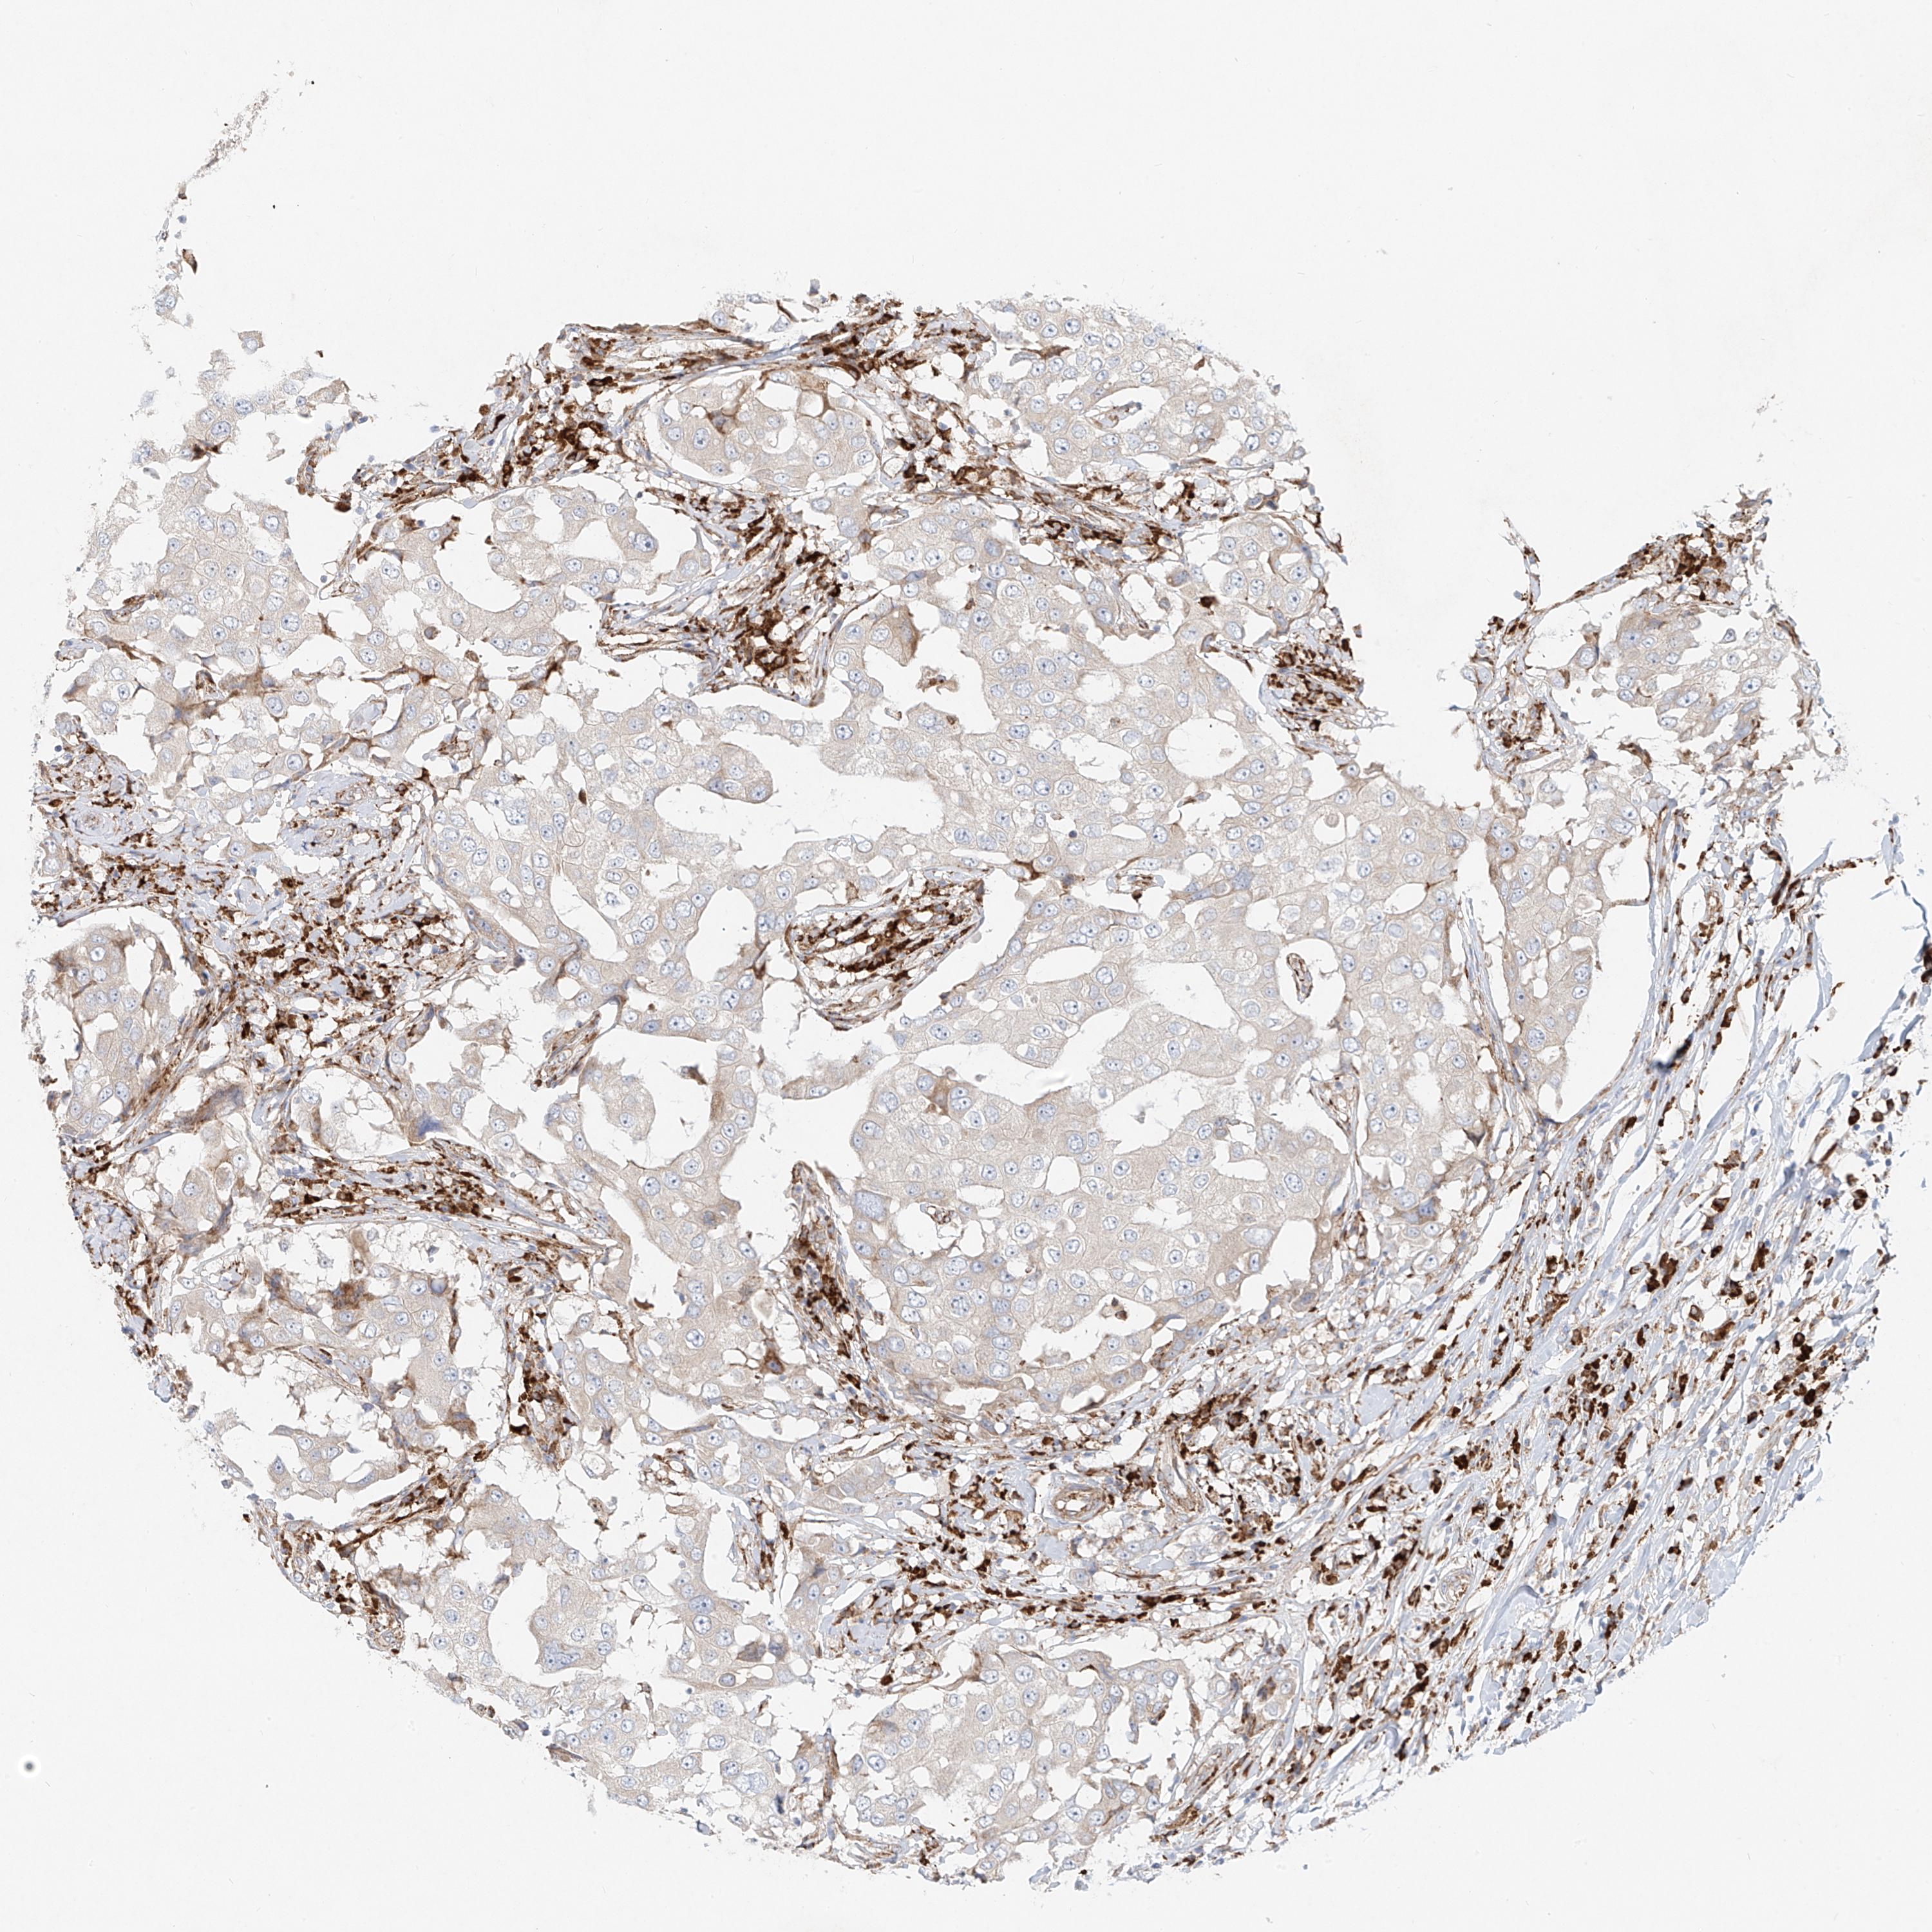

CANCER BREAST CANCER Show tissue menu

BRCA TCGA BRCA VALIDATION PROTEIN EXPRESSION